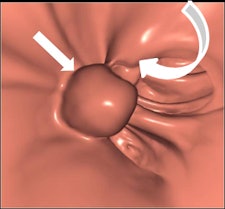

Along with his colleague Dr. Stefaan Gryspeerdt, Lefere has addressed CTC's potential pitfalls in a comprehensive paper published online January 4 in Insights into Imaging. Their top tips are to perform state-of-the-art CTC (preparation based on fecal tagging, along with colonic distension with CO2 plus injector, dual positioning, and smooth muscle relaxation), remember the general principles of interpretation, and take special care when examining the rectum and caecum.